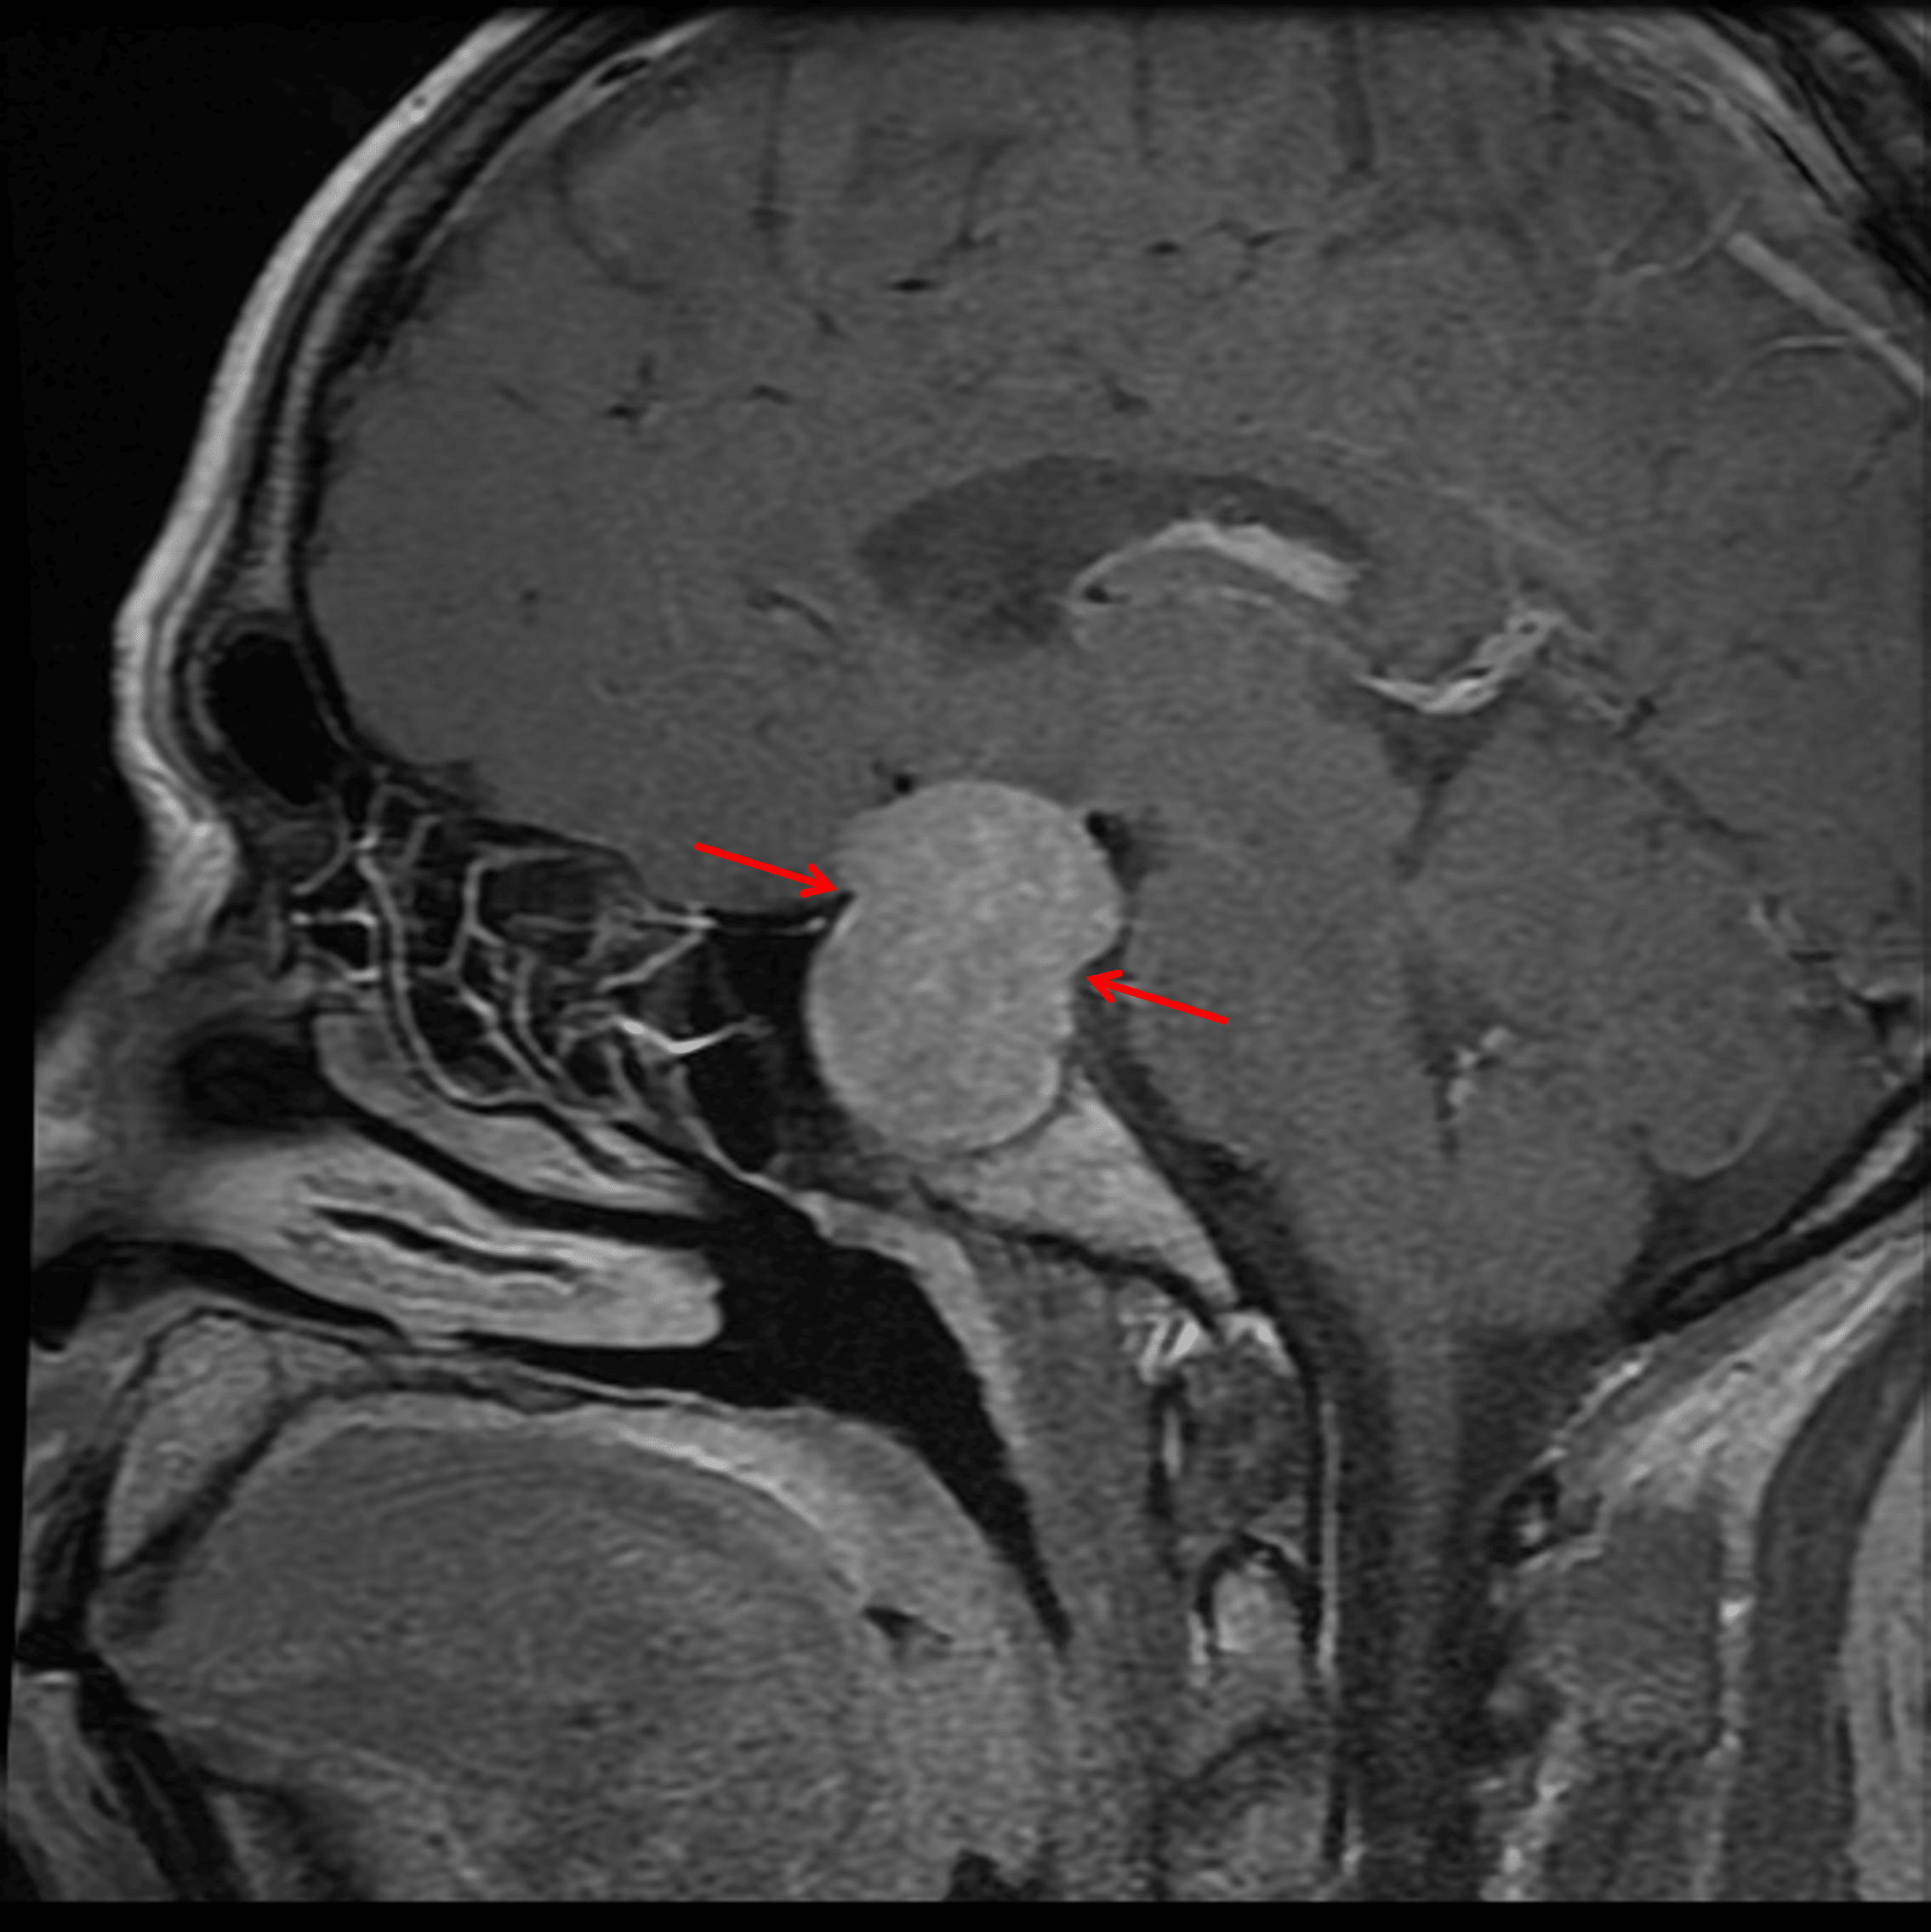

- T1/T2 isointense, homogeneously enhancing sellar and suprasellar mass measuring 2.5 x 2.4 x 4 cm

- Waist-like narrowing of the mass in the region of the diaphragma sellae

- The mass contacts and uplifts the optic chiasm

Diffusely enhancing sellar and suprasellar mass with waist-like narrowing in the region of the diaphragma sellae (red arrows).